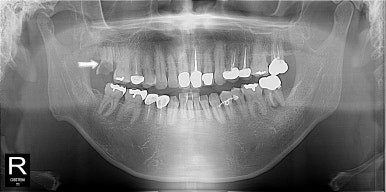

원래 발치하기로 했던 치아는 더 썩어서 부러져 있어고 좌측 아래 작은 어금니도 그동안 충치가 많이 진행되어 신경치료가 필요한 상황이었다.

발치와 첫 신경치료는 수면마취로 진행하고 조심스럽게 말을 건내본다.

무사히 비수면으로 신경치료도 마치고 크라운 치료까지 잘 받아주셨다.

그래도 아직 임플란트 수술까지는 무서워하시니 수술은 다시 수면치료